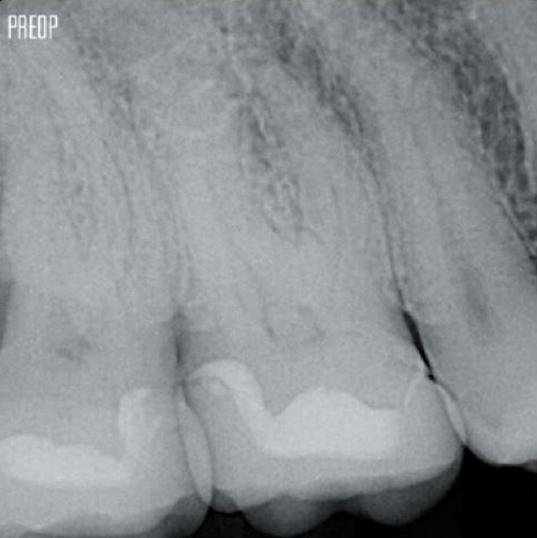

Fotos cortesía del Dr. Ahmed Salman

Más conservación de dentina. Se garantiza la conformación, irrigación y obturación adecuadas.

Un tratamiento exitoso de conducto radicular comienza con un acceso adecuado a la cámara pulpar. El procedimiento ideal proporciona acceso a la entrada del conducto radicular con una pérdida mínima de dentina.

Se recomienda utilizar una cavidad endodóntica conservadora (Conservative Endodontic Cavity, CEC) con el sistema TruNatomy®.